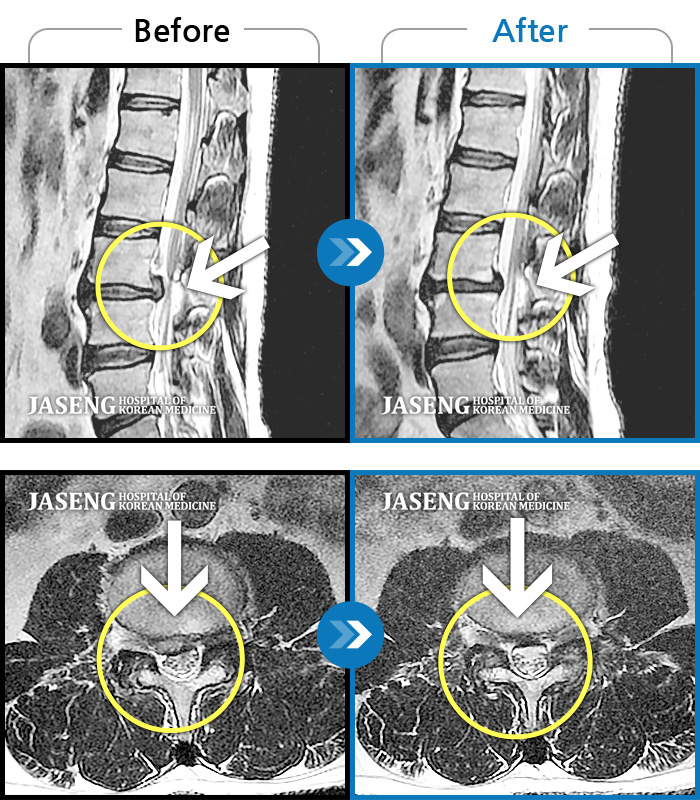

허리디스크

일산 · 김진수 원장

우측 골반 통증이 심하고 우측 하지로 당김과 저림이 지속되었습니다. 야간통이 심하여 야간 수면 제한이 되는 등 중등도 이상의 통증을 호소하는 상태였습니다.

촬영시기

2021.03.22 ~ 2025.09.30

2025.10.30